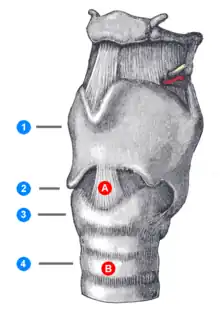

Open surgical tracheotomy (OST)

The typical procedure done is the open surgical tracheotomy (OST) and is usually done in a sterile operating room. The optimal patient position involves a cushion under the shoulders to extend the neck. Commonly a transverse (horizontal) incision is made two fingerbreadths above the suprasternal notch. Alternatively, a vertical incision can be made in the midline of the neck from the thyroid cartilage to just above the suprasternal notch. Skin, subcutaneous tissue, and strap muscles (a specific group of neck muscles) are retracted aside to expose the thyroid isthmus, which can be cut or retracted upwards. After proper identification of the cricoid cartilage and placement of a tracheal hook to steady the trachea and pull it forward, the trachea is cut open, either through the space between cartilage rings or vertically across multiple rings (cruciate incision). Occasionally a section of a tracheal cartilage ring may be removed to make insertion of the tube easier. Once the incision is made, a properly sized tube is inserted. The tube is connected to a ventilator and adequate ventilation and oxygenation is confirmed. The tracheotomy apparatus is then attached to the neck with tracheotomy ties, skin sutures, or both.[11][12]

Towards the end of the 16th century, anatomist and surgeon Hieronymus Fabricius (1533–1619) described a useful technique for tracheotomy in his writings, although he had never actually performed the operation himself. He advised using a vertical incision and was the first to introduce the idea of a tracheostomy tube. This was a straight, short cannula that incorporated wings to prevent the tube from advancing too far into the trachea. He recommended the operation only as a last resort, to be used in cases of airway obstruction by foreign bodies or secretions. Fabricius' description of the tracheotomy procedure is similar to that used today. Giulio Cesare Casseri (1552–1616) succeeded Fabricius as professor of anatomy at the University of Padua and published his own writings regarding technique and equipment for tracheotomy. Casseri recommended using a curved silver tube with several holes in it. Marco Aurelio Severino (1580–1656), a skillful surgeon and anatomist, performed multiple successful tracheotomies during a diphtheria epidemic in Naples in 1610, using the vertical incision technique recommended by Fabricius. He also developed his own version of a trocar.[37]